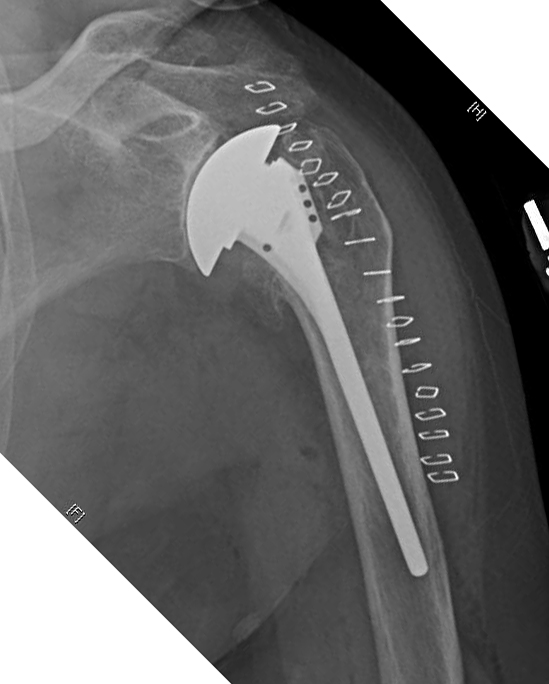

Other proposed advantages of the stemless humeral implant are reduction of the risk of traumatic periprosthetic humeral shaft fracture as a result of a stress riser at the distal tip of the implant, decrease in the risk of stress shielding, and reduction of the risk of stem revision. However, these risks area also reduced by the use of a thin, smooth, impaction grafted stem as shown below.

Clinical experience has indicated that stemless prostheses have their own learning curve and set of potential problems of fixation and positioning as shown in the films below.

This approach enables precise positioning of a humeral component with a smaller stem, secure safe fixation, and ease of prosthesis exchange should revision become necessary. Note the absence of cortical contact with the tip of the prosthesis and the absence of stress shielding.